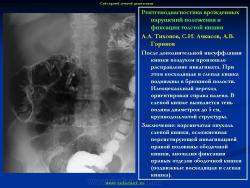

Варианты и аномалии развития толстой кишки.